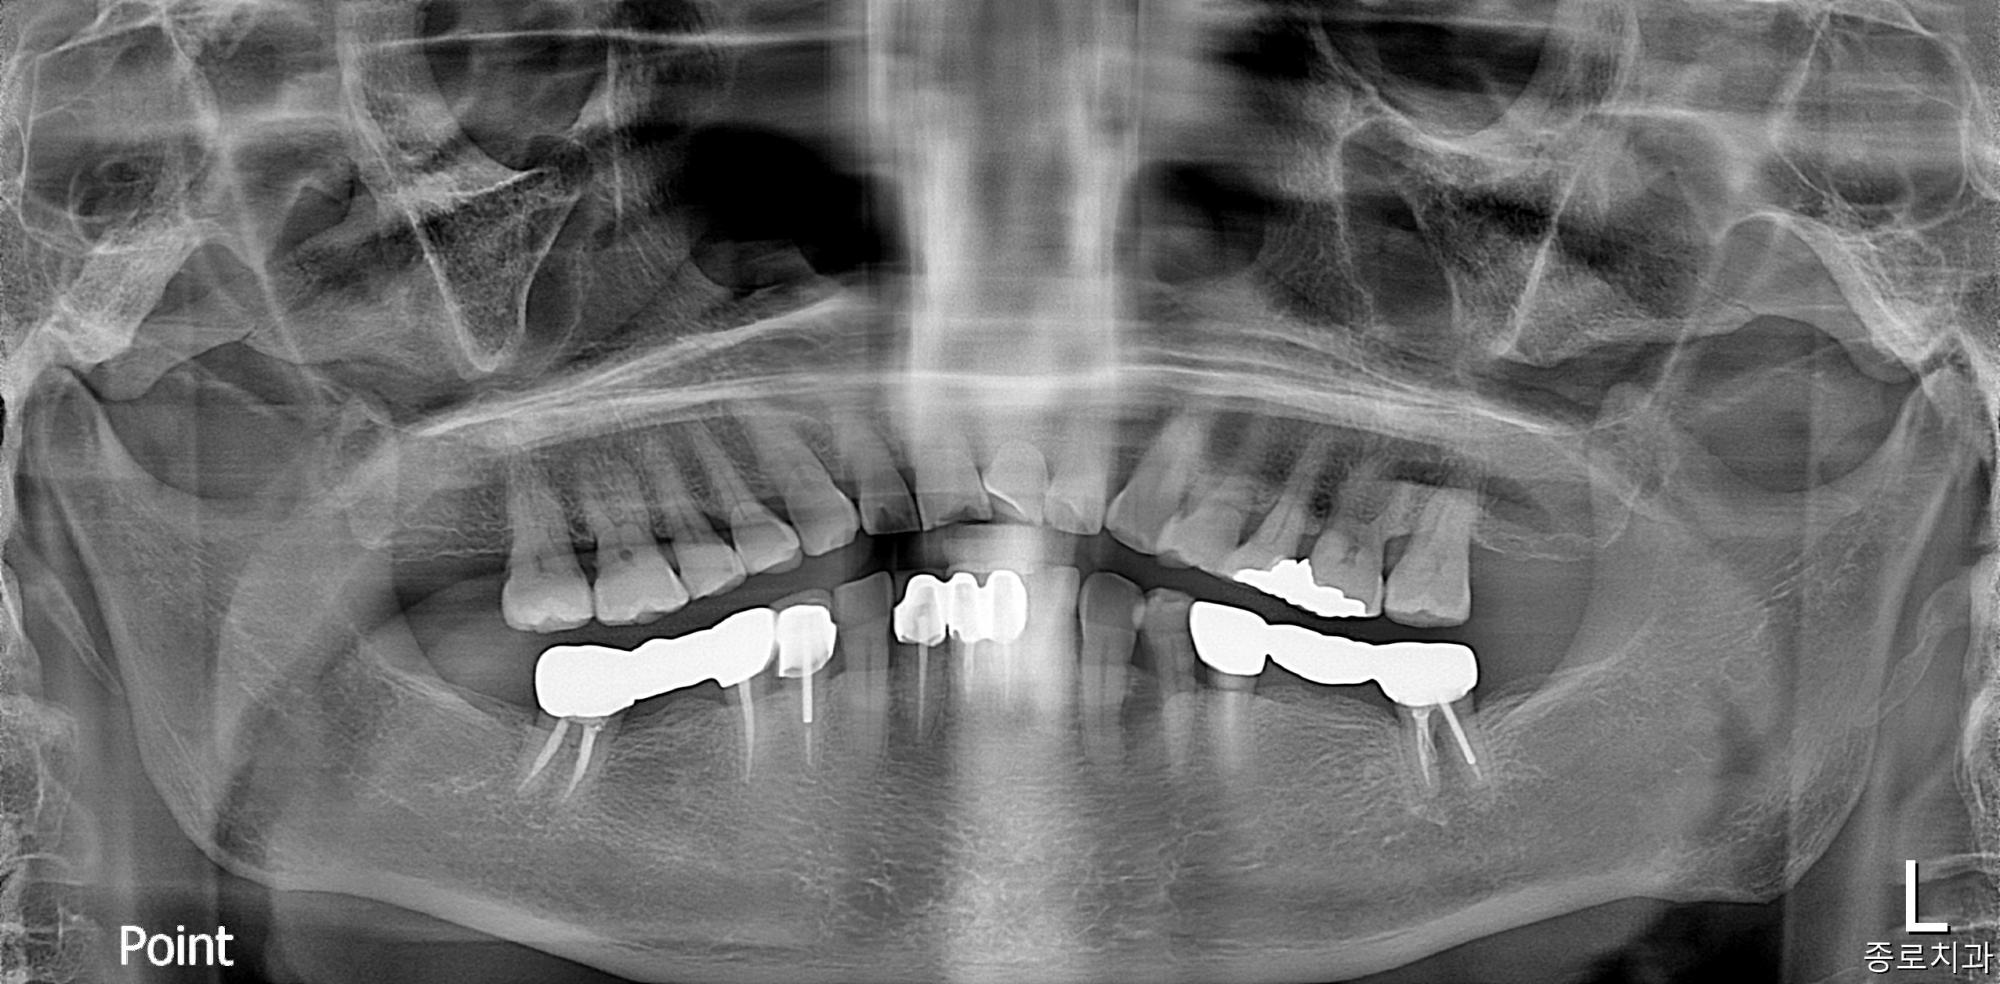

전/후 사진갤러리